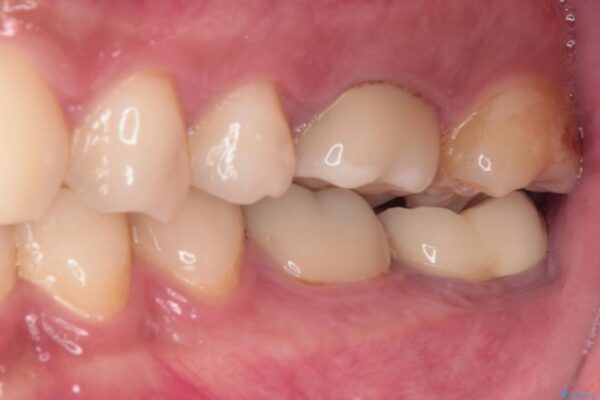

• 海外赴任前に治したい 割れてしまった奥歯のオールセラミッククラウン 治療後画像